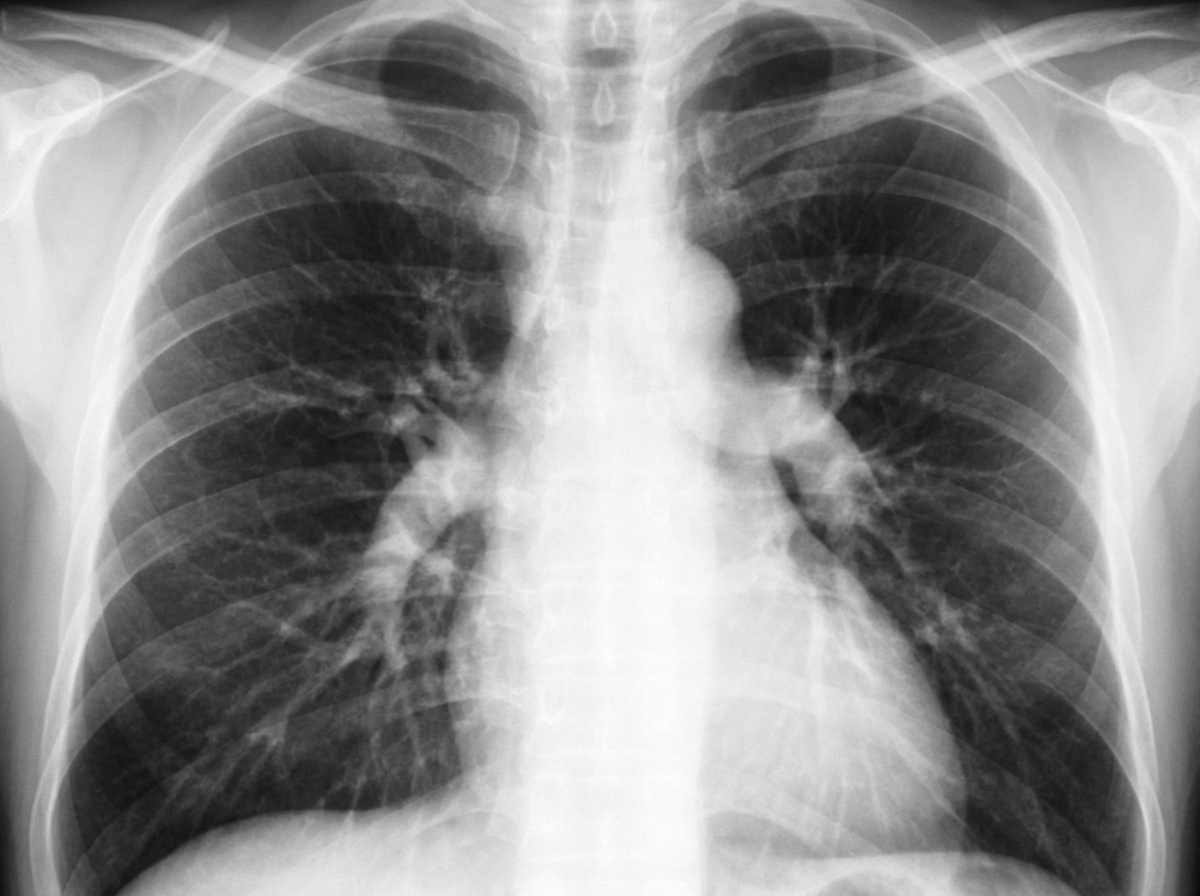

Explanation: ***Pulmonary artery hypertension*** - **Enlarged central pulmonary arteries** with **right heart enlargement** and **peripheral vascular pruning** are classic chest X-ray findings in pulmonary arterial hypertension. - The combination of prominent **main pulmonary artery segment** and **dilated right ventricle** creates the characteristic appearance on CXR. *Aortic dissection* - Typically presents with a **widened mediastinum** and abnormal **aortic contour** on chest X-ray, not enlarged pulmonary arteries. - Associated with **acute chest pain** radiating to the back, not the chronic progressive dyspnea seen in PAH. *Coarctation of aorta* - Chest X-ray shows **rib notching** from collateral circulation and **post-stenotic dilatation** of the descending aorta. - The **"3 sign"** or **"reverse E sign"** may be visible on the left heart border, not pulmonary artery enlargement. *Boot shaped heart* - Characteristic of **Tetralogy of Fallot** with **upturned cardiac apex** and **concave pulmonary artery segment**. - Associated with **decreased pulmonary vascular markings** (oligemic lung fields), opposite to the findings in PAH.

Explanation: **Explanation:** **Aortic dissection** is a life-threatening emergency characterized by a tear in the tunica intima, leading to the creation of a "false lumen" within the aortic wall. **Why CT is the Investigation of Choice:** **Contrast-Enhanced Computed Tomography (CECT)**, specifically **CT Angiography (CTA)**, is the gold standard and investigation of choice because of its high sensitivity and specificity (>95%). It is rapid, widely available, and non-invasive. It accurately identifies the **intimal flap** (separating the true and false lumens), the extent of the dissection, and involvement of major branch vessels, which is critical for surgical planning. **Analysis of Other Options:** * **USG (Transthoracic Echocardiography):** While useful for screening or detecting proximal (Type A) dissections and pericardial effusion, it has poor visualization of the descending aorta. *Transesophageal Echocardiography (TEE)* is highly accurate but invasive and often unavailable in emergency settings. * **MRI (MRA):** This is the most accurate imaging modality; however, it is **not** the investigation of choice in an acute setting because it is time-consuming, difficult to monitor unstable patients within the magnet, and less available. * **Digital Subtraction Angiography (DSA):** Once the gold standard, it is now rarely used for diagnosis as it is invasive and cannot visualize the aortic wall or thrombus, only the lumen. **Clinical Pearls for NEET-PG:** * **Classic Sign on CT:** The "Intimal Flap" (visualized as a linear lucency) and the "Bird’s Beak Sign" (seen in the false lumen). * **Chest X-ray:** May show a **widened mediastinum** (most common finding) or the "Calcium Sign" (displacement of intimal calcification >1cm). * **Stanford Classification:** Type A involves the ascending aorta (Surgical emergency); Type B involves only the descending aorta (Medical management).

Explanation: **Explanation:** **1. Why MRI is the correct answer:** MRI (specifically MR Angiography) is considered the **Gold Standard** and the investigation of choice for aortic dissection due to its near 100% sensitivity and specificity. It provides superior anatomical detail, accurately identifies the entry/exit tears, determines the involvement of branch vessels, and can detect associated aortic regurgitation without the need for iodinated contrast or ionizing radiation. **2. Analysis of Incorrect Options:** * **Aortography:** Formerly the gold standard, it is now rarely used as it is invasive, requires large doses of contrast, and may miss the diagnosis if the false lumen is thrombosed. * **CT Scan (Contrast-Enhanced CT/CTPA):** In clinical practice, CECT is the **investigation of choice in emergency/hemodynamically unstable patients** because it is rapid and widely available. However, in a theoretical "best test" scenario without clinical context, MRI is superior. * **X-ray Chest:** This is the initial screening tool. While it may show a "widened mediastinum" or "calcium sign," it is neither sensitive nor specific enough to confirm a diagnosis. **3. NEET-PG High-Yield Pearls:** * **Investigation of choice (Overall/Gold Standard):** MRI. * **Investigation of choice (Emergency/Unstable patient):** CT Scan (CECT). * **Bedside investigation of choice:** Transesophageal Echocardiography (TEE) — highly useful for unstable patients or those with renal failure. * **Stanford Classification:** Type A (involves ascending aorta; surgical emergency) vs. Type B (descending aorta only; medical management). * **Classic Sign on CT:** "Intimal flap" separating the true and false lumens.